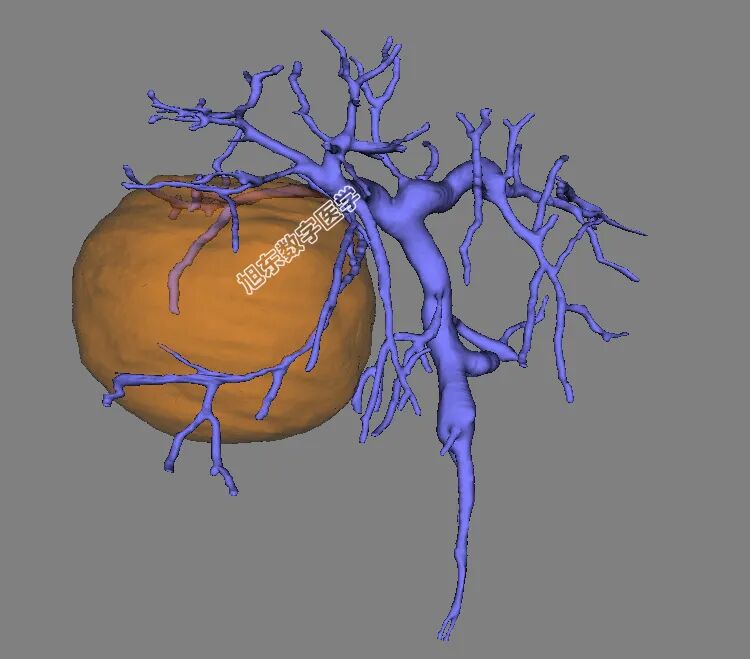

占位与动脉血管解剖关系

占位与门静血管解剖关系

占位与肝静脉解剖关系